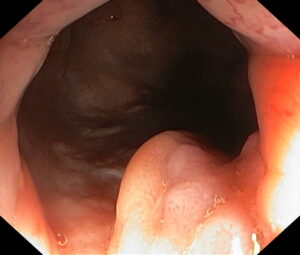

Атлас

В эндоскопическом атласе обычно представлены изображения и видео, полученные во время процедур, проводимых врачами-эндоскопистами. Эти изображения и видео могут использоваться для обучения студентов медицинских учебных заведений, повышения квалификации медицинских работников, а также для консультации врачей при диагностике и лечении различных заболеваний.